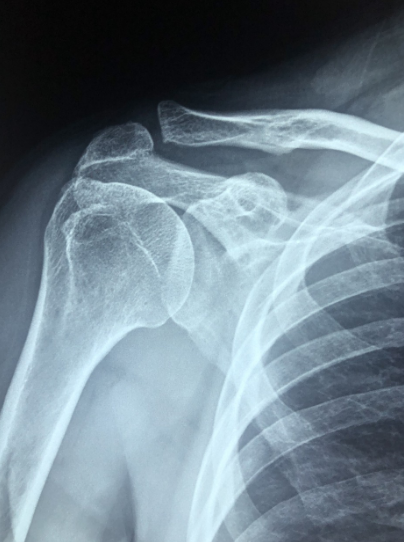

석회성 건염은 어깨 관절의 퇴행성 변화로 인해 발생하는 질환이며, 주로 어깨 인대에 석회가 돌처럼 단단하게 뭉칩니다. 이로 인해 어깨가 무거워지고 활동이 불편해질 수 있습니다. 초기에는 어깨의 무거운 느낌과 활동이 제한되는 증상이 나타나며, 석회화가 진행되면 팔을 들 때 뜨거운 느낌이 들 수 있습니다. 치료는 X레이 촬영을 통해 진단을 받고, 적절한 치료로 증상을 완화시킬 수 있습니다. 따라서 통증이 지속되면 반드시 의료진을 방문하여 진단과 치료를 받아야 합니다.